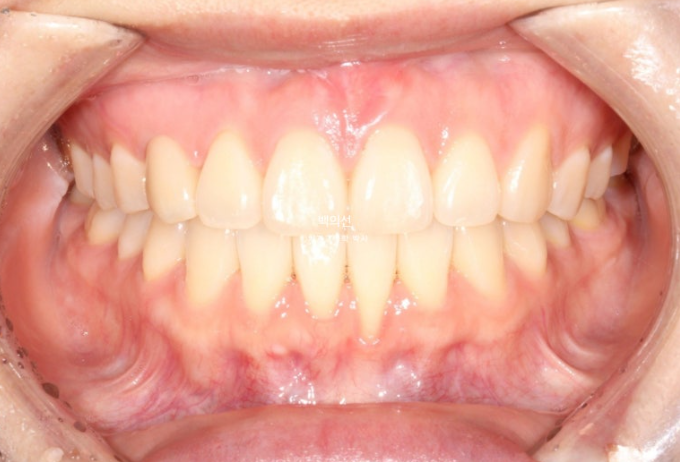

기울어져있던 앞니 치축은 완전히 개선되었으며 중심선은 잘 맞습니다.

크라운 수복이 끝난 후 어태치먼트를 전부 제거하고 치료를 마쳤습니다.

25.07

어떤게 크라운이고 어떤게 자연치 송곳니인지 분간이 잘 되지 않습니다.

교합은 좋습니다.

이제 전후비교 보겠습니다.

24.10~25.07

치료기간은 10개월 입니다.

주목할만한 점은 바로 치료 후 잇몸퇴축이 완화된 점입니다.

잇몸이 내려간 치아의 튀어나온 뿌리를 안으로 넣어줌으로써, 잇몸이 내려가 뿌리가 노출된 면적이 줄어들었습니다.

그외 소량의 치간삭제를 통한 틀랙트라이앵글의 개선도 눈에 띕니다.

개선된 미소와 스마일라인, 비스듬히 기울어진 앞니 각도의 개선

깔끔한 스마일라인이 돋보입니다.